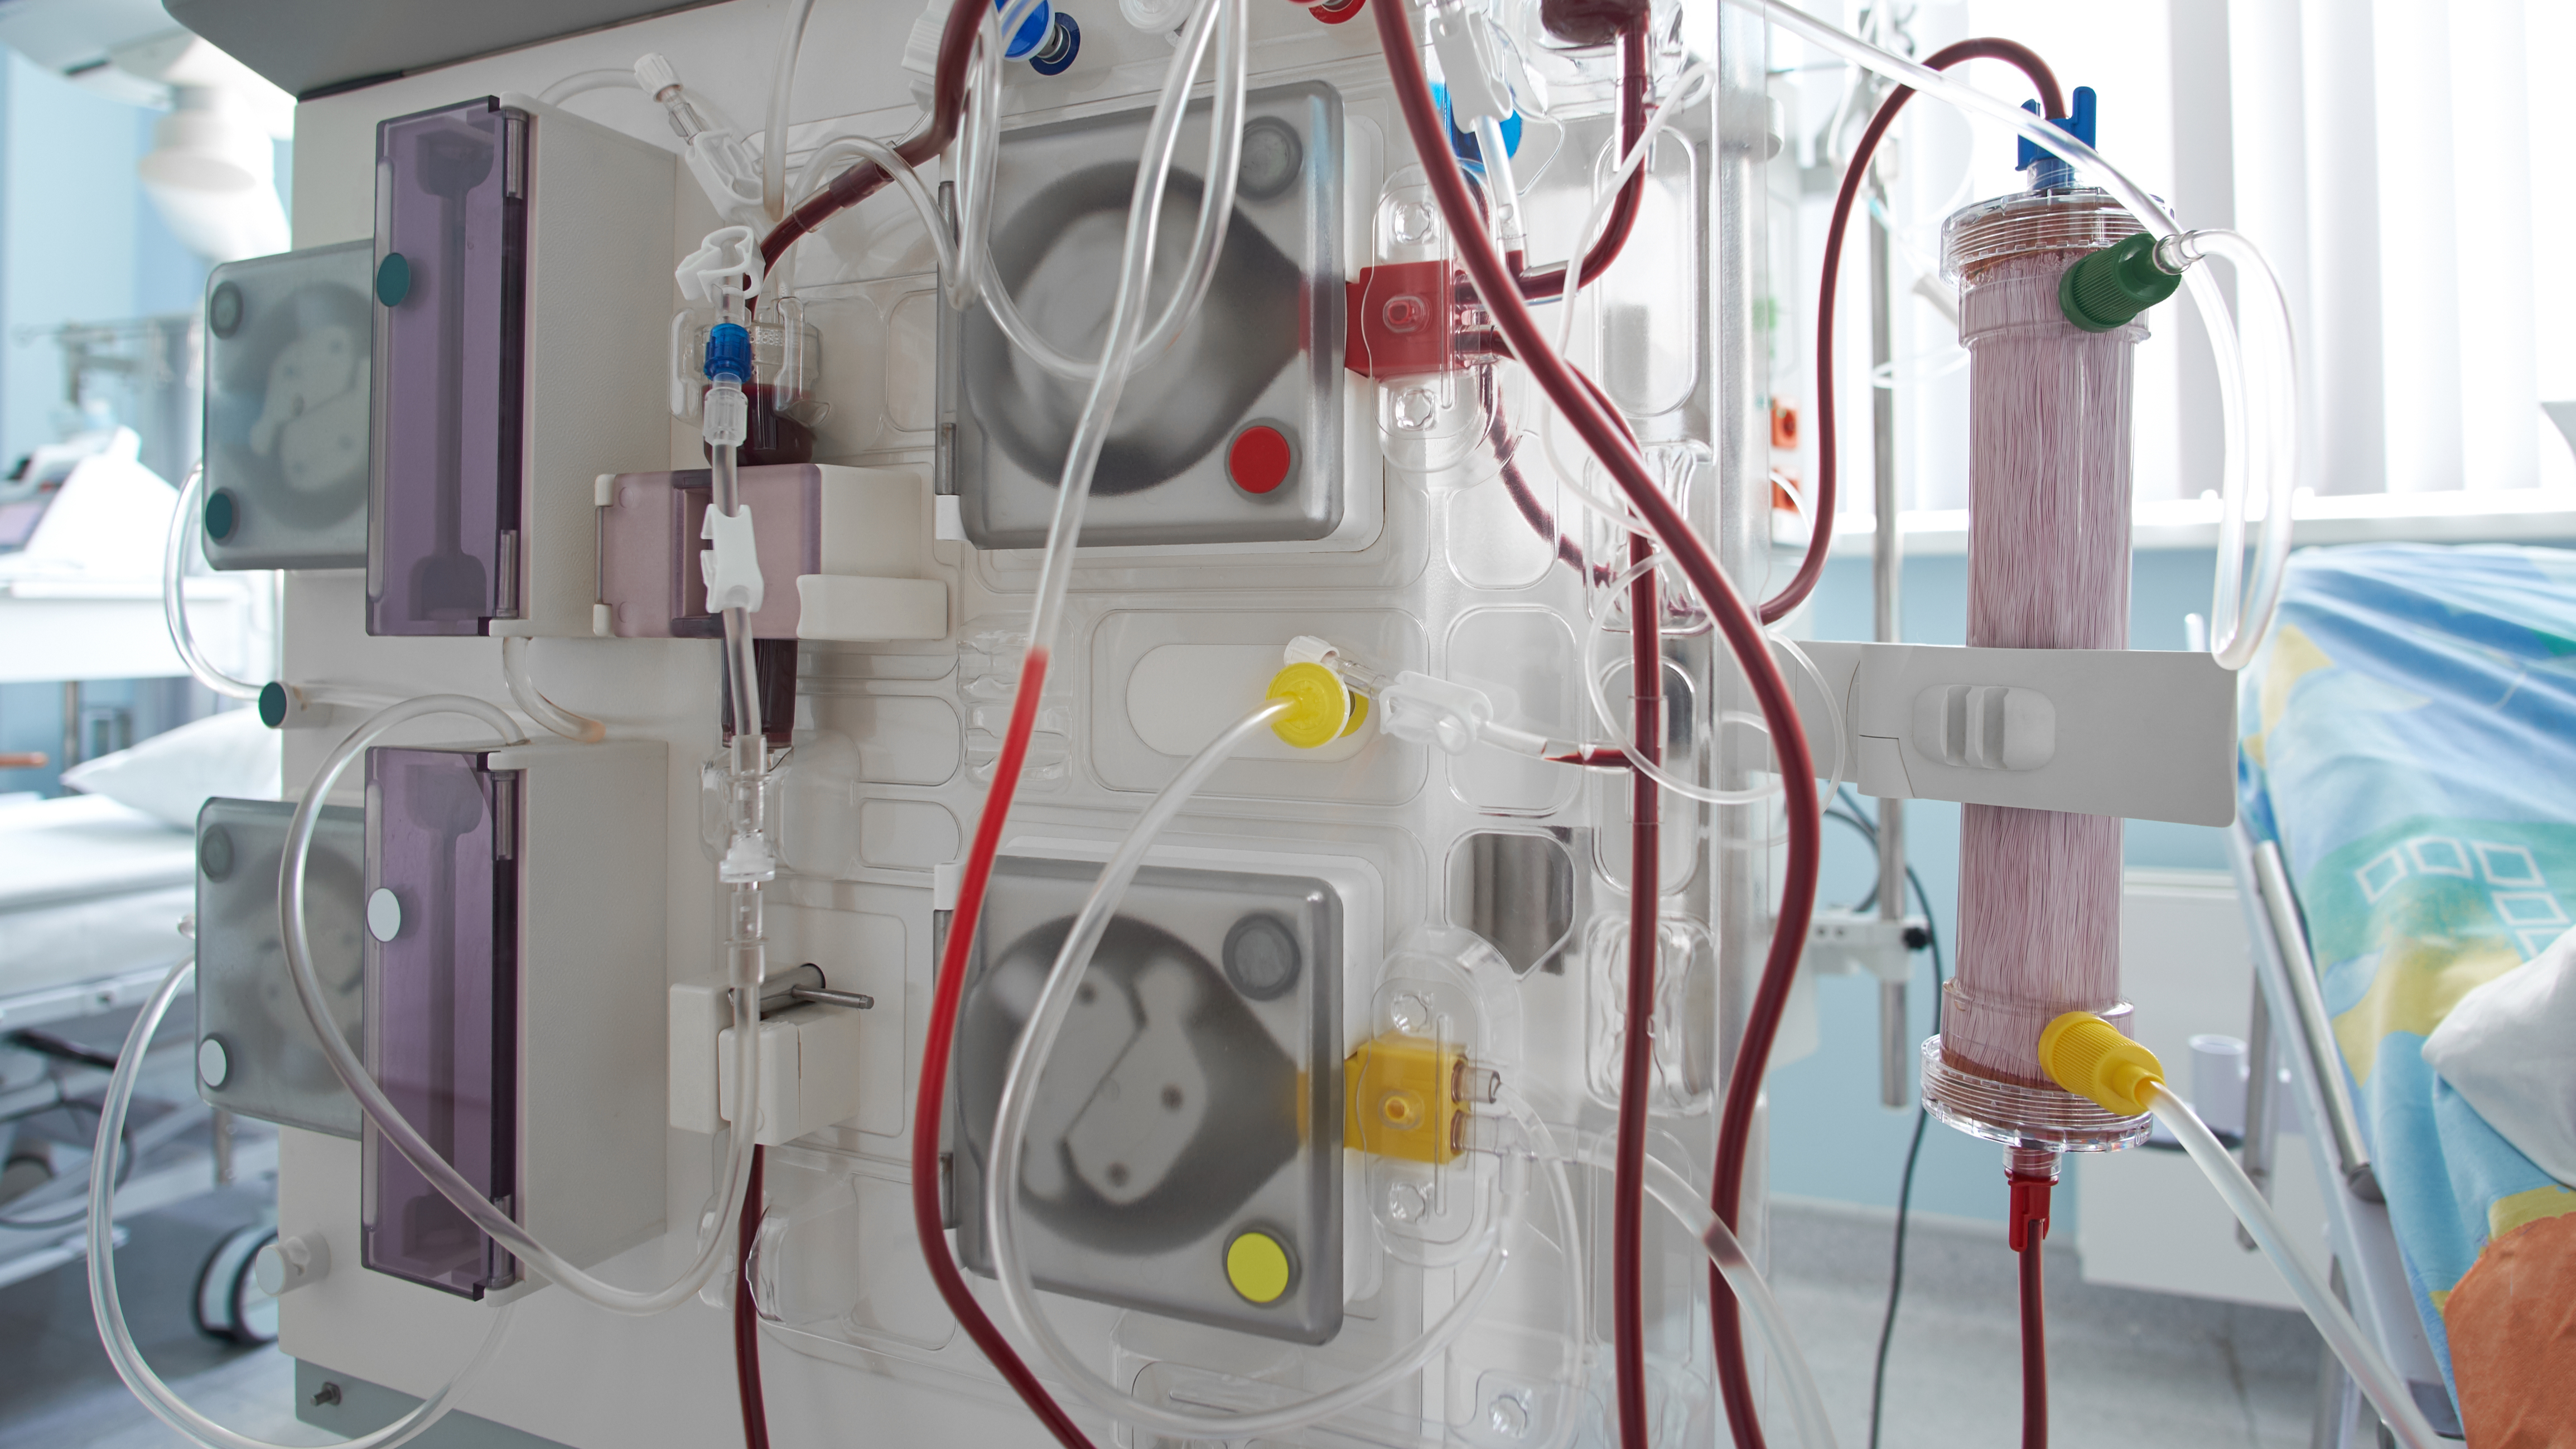

Revolutionizing hemodialysis treatment

and thereby improving quality of life for millions patients with chronic kidney disease

Patients with end-stage kidney disease (ESKD) require a lifesaving modality to replace kidney function and to prevent mortality from accumulated waste products. Due to kidney donor shortages, dialysis is often the only possible treatment: ~80% of ESKD patients are on dialysis.

The high-flow vascular access site required for dialysis frequently causes serious complications. XS Innovations has invented the solution to mitigate these complications and increases quality of life for ESKD patients.